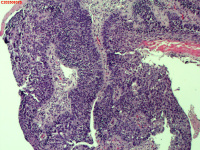

纤支镜咬检

性别

男

年龄

40岁

临床诊断

肺癌?

一般病史

增强CT提示右肺中叶粘液栓;气管镜见右肺中叶外侧段新生物,考虑恶性可能。

标本名称

图1

鳞状细胞癌